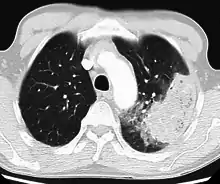

A chest radiograph is frequently used in diagnosis.[23] In people with mild disease, imaging is needed only in those with potential complications, those not having improved with treatment, or those in which the cause is uncertain.[23][67] If a person is sufficiently sick to require hospitalization, a chest radiograph is recommended.[67] Findings do not always match the severity of disease and do not reliably separate between bacterial and viral infection.[23]

X-ray presentations of pneumonia may be classified as lobar pneumonia, bronchopneumonia, lobular pneumonia, and interstitial pneumonia.[73] Bacterial, community-acquired pneumonia classically show lung consolidation of one lung segmental lobe, which is known as lobar pneumonia.[41] However, findings may vary, and other patterns are common in other types of pneumonia.[41] Aspiration pneumonia may present with bilateral opacities primarily in the bases of the lungs and on the right side.[41] Radiographs of viral pneumonia may appear normal, appear hyper-inflated, have bilateral patchy areas, or present similar to bacterial pneumonia with lobar consolidation.[41] Radiologic findings may not be present in the early stages of the disease, especially in the presence of dehydration, or may be difficult to interpret in the obese or those with a history of lung disease.[24] Complications such as pleural effusion may also be found on chest radiographs. Laterolateral chest radiographs can increase the diagnostic accuracy of lung consolidation and pleural effusion.[40]

A CT scan can give additional information in indeterminate cases[41] and provide more details in those with an unclear chest radiograph (for example occult pneumonia in chronic obstructive pulmonary disease). They can be used to exclude pulmonary embolism and fungal pneumonia, and detect lung abscesses in those who are not responding to treatments.[40] However, CT scans are more expensive, have a higher dose of radiation, and cannot be done at bedside.[40]